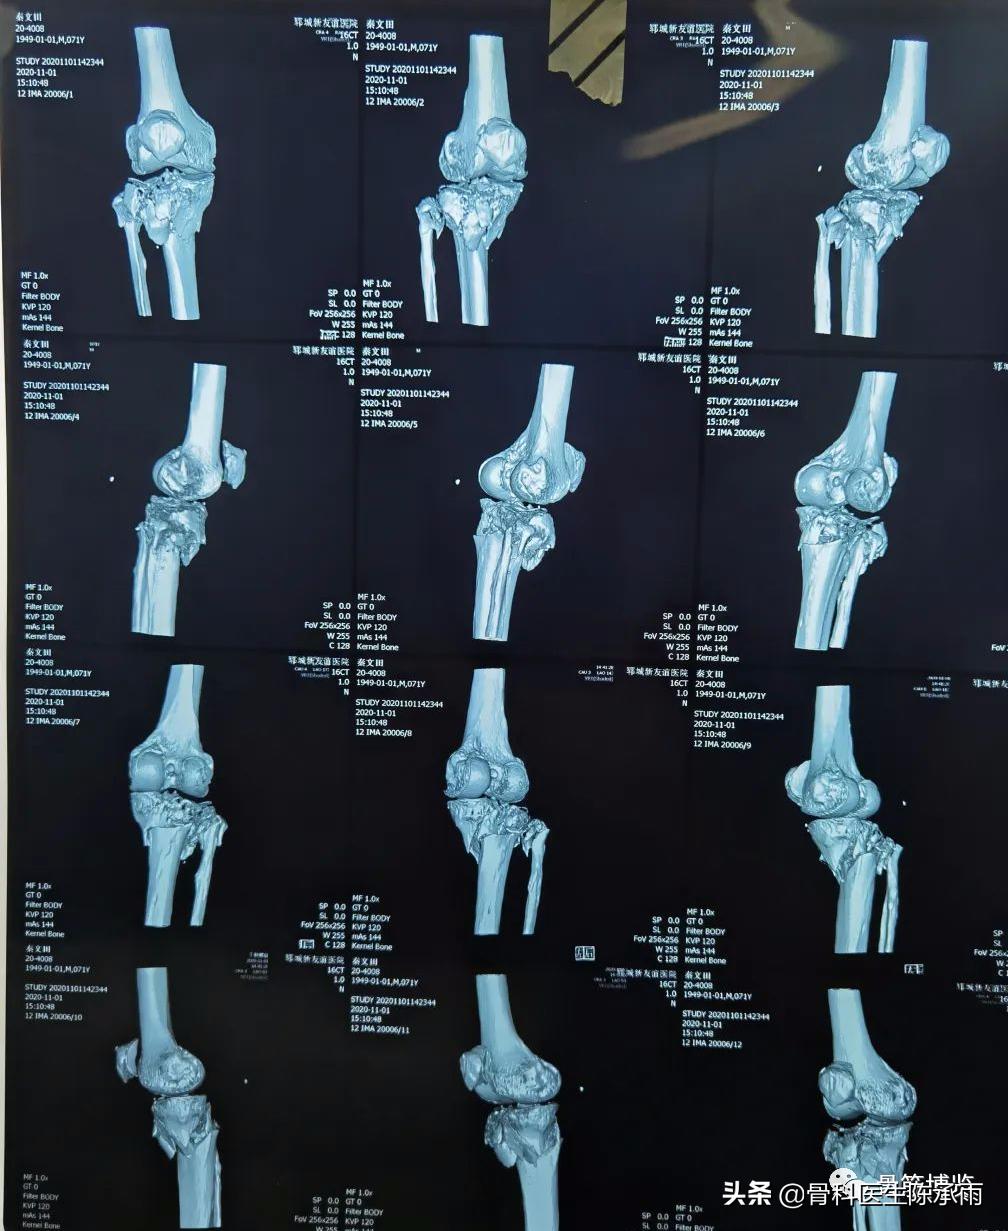

下例胫平台骨折皮肤条件差,内侧板取两端小切口置入内板固定。胫骨结节处撕脱骨折以1枚拉力螺钉固定。